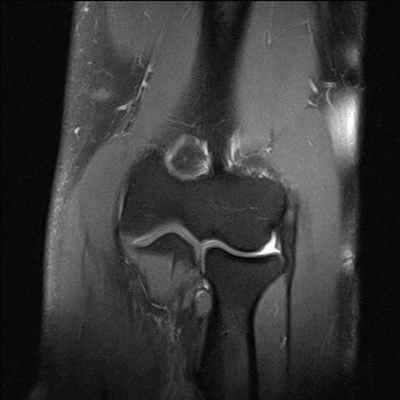

(Слева) МРТ, PDВИ, режим подавления сигнала от жира, коронарный срез: определяется полный разрыв ЛПС в месте прикрепления к ладьевидной кости с расширением ладьевидно-полулунного промежутка. Эти признаки характерны для развития ладьевидно-полулунной диссоциации.

(Справа) МРТ, PDВИ, режим подавления сигнала от жира, коронарный срез, полученный в ладонном направлении по сравнению с предыдущим изображением: у этого же пациента определяется разрыв лучеладьевидно-головчатой связки. Разрыв этой наружной связки вместе с сопутствующим разрывом ЛПС способствует развитию диссоциации. (Слева) МРТ, PDВИ, режим подавления сигнала от жира, коронарный срез: определяется нормальная дугообразная связка. Она является стабилизирующим соединением наружных связок, включающих в себя ладьевидно-головчатую и трехгран-но-крючковидно-головчатую. Слабость данной связки приводит к нестабильности пястных костей (НПК).

(Справа) МР-артрография, Т1ВИ, коронарный срез: определяется повреждение хряща и субхондральный склероз дистального отдела полулунной кости, в месте сочленения ее с головчатой. Такой тип артроза предполагает наличие динамической НПК. Статическая рентгенография при ранней НПК обычно демонстрирует отсутствие патологии отклонения осей костей. (Слева) МРТ, STIR, коронарный срез: определяется полный разрыв ЛПС с расширением суставной щели. Обратите внимание на существенное сужение суставной щели головчато-полулунного сочленения. Эти патологические изменения возникли вследствие начального проксимального смещения головчатой кости при прогрессирующем коллапсе кисти (ЛППК).